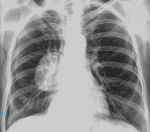

Добрый день. Женщина 65 лет. В 2014 году на флюорограмме чисто. Жалоб нет. В анамнезе (2015 г) оперирована по поводу cr желудка. Ваши мнения. Спасибо.

По прямой проекции, образование переднего средостения. С боковой диффряд расширился.

Я бы предположил образование плевры, и КТ для уточнения

По плотности и контуру м.б. и жидкость к выше перечисленному.

Тут бы УЗИ плевральных полостей. Сдаётся мне- в плевре оно.

Считаю, что образование из легкого. Предполагаю заполненную кисту. Учитывая пристеночный спонтанный пневматоракс справа, киста там не одна.)

Ни чего не имею против кисты, но очень сложно. 1- процесс не соответствует сегментарно-долевому строению.

2- имеет место второй такой же процесс прилежащий к париетальной плевре или как то связанный с ней( боковая пр.)

3- онколог. анамнез.

Боковую Т-гр, КТ.

Тень определенно в легком, расположена практически вплотную к задней поверхности грудины. Т.е. между грудиной и объемным образованием небольшая прослойка легочной ткани (граница с воздухом), поэтому и контур его так плохо различим. Учитывая онконанамнез я больше за метастаз. К тому же второе образование определенно исходит из плевры, на боковом расположено за округлой тенью, т.е. левее, но также за грудиной. А что касается переломов ребер, то вполне возможно когда-то был прелом заднебокового отрезка 6-го ребра справа. Пнемоторакс может быть связан и с прорастанием опухоли в плевру. Хотелось бы увидеть прямой снимок в другой обработке, чтобы тень сердца не перекрывала вид.

Пнемоторакс не исключается, т.к. кроме линии образованной краем молочной железы несколько медиальнее выявляется ещё одна  линия (плевры?). Крупное круглое гомогенное тенеобразование расположено внутри лёгкого (Правило Ленка ), контуры ровные, близлежащая плевра утолщена. Диффряд широкий: шаровидная пневмония (м.б.и абсцесс), онкообразование (м.б. и одиночный метастаз), киста (не исключаю сочетания патологии - и потому так всё интересно выглядит) и согласен с предыдущим мнением, надо томографировать.

Больше похоже на солитарный метастаз в плевру,создаётся впечателние, что какое-то колчество выпота в плевральной полости есть и почему же при этом (опухолевом поражении плевры) не может быть проявлений пневмотакса (нарушение целостности висцеральной плевры).

Поддержу версию Almo про солитарный мтс и небольшое количество выпота. А пневмоторакса нет!winkМягкие ткани груди это. Зуб даю, хотя и нелишний!smiley

Ваша версия, Игорь, не менее интересная. Я имею в виду о жидкостном содержимом этого образования, т.е.кисту ( любого генеза)  в диф.ряд обязательно нужнотвключить. А локализация -на уровне 3-5 сегментов справа. Сомнений нет, что оно в лёгком, но вторую пристеночную тень, думаю, формирует утолщенная плевра. А уж за счёт чего....Самый простой способ узнать, что это такое-УЗИ.

Солитарных мтс рака  желудка в плевру не встречал,как правило сыплет множественными, мелкими .Думаю жидкостое( а может и нет) образование округлой формы и пристеночное тоже связаны с метастатическим процессом.Вопрос, возникший по локализации округлого образования, так и не снят: в легком,  м\долевой, плевральной полости?  Думаю Узи не решит, предпочел бы боковые Т-гр.не говоря о КТ.

На мой взгляд похоже на фиброзную опухоль плевры..., плиз...